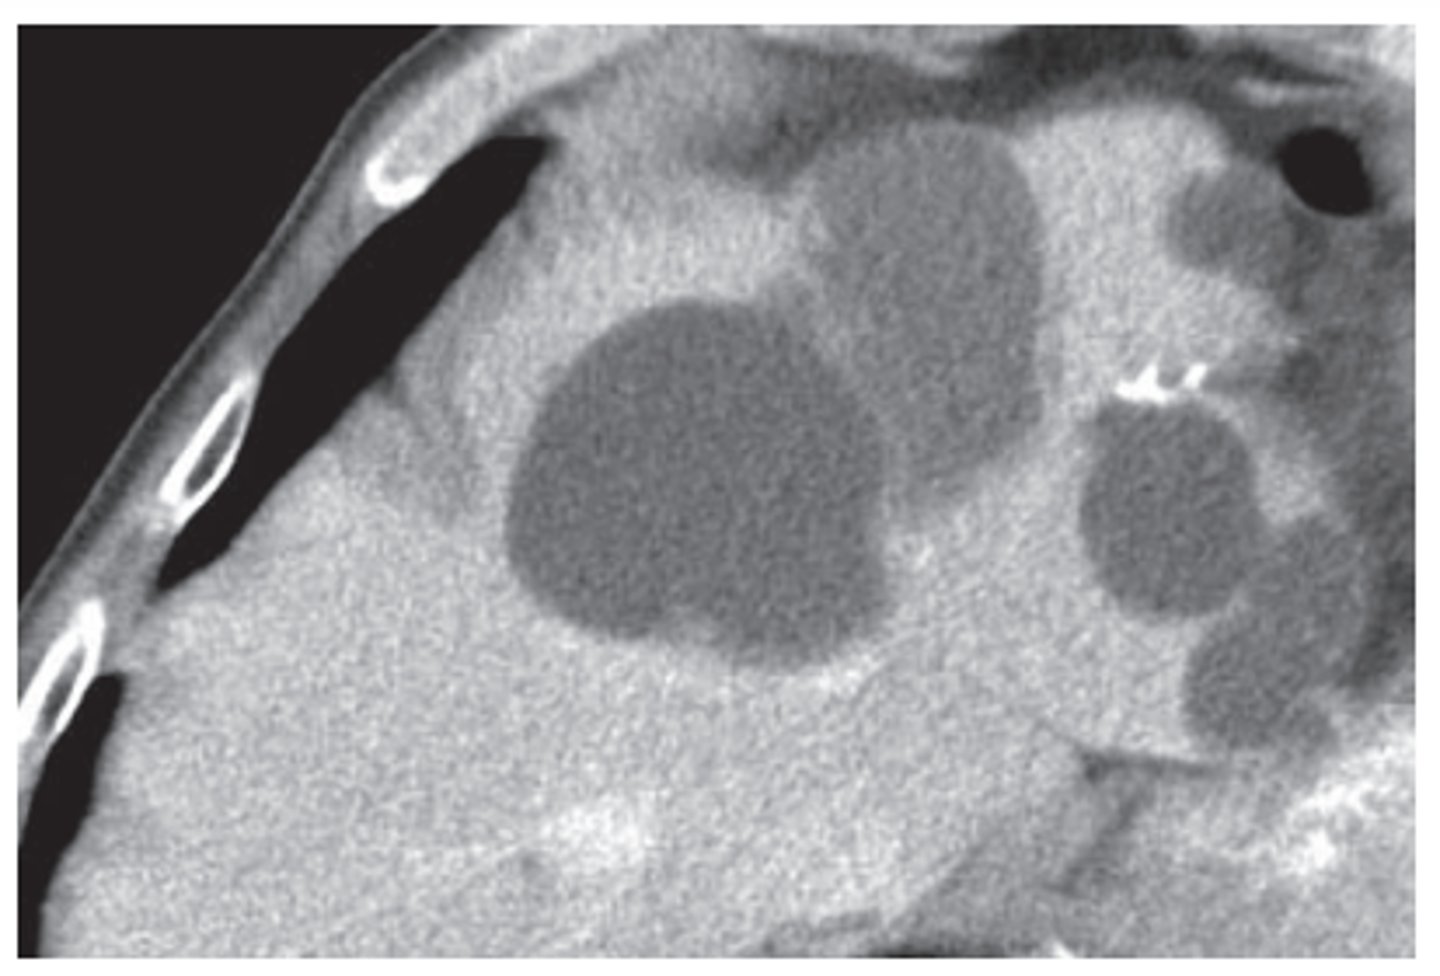

hepatic cysts

common, usually incidental findings, lower density than liver, clearly defineed